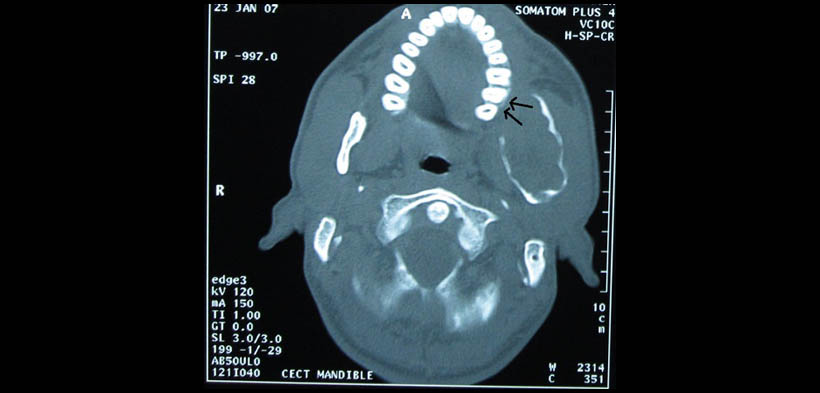

Los hallazgos inusuales de la TC pueden evidenciarse en aquellas lesiones de gran crecimiento y larga data que pueden causar desfiguración de las estructuras circundantes debido a la presión, sin la necesidad de invadir dichas estructuras. Arora, et al realizaron un reporte de caso de un ameloblastoma pleximorme localizada en el cuerpo ángulo y rama mandibular izquierdo, y cuyo crecimiento produjo la deformación de la hemimaxila de dicho lado, considerándose a este hallazgo como algo inusual (fig.1-4)(1).

Fig. 3. TAC, vista axial. Se visualiza el crecimiento de la lesión y la deflexión que produce en la arcada posterior izquierda.